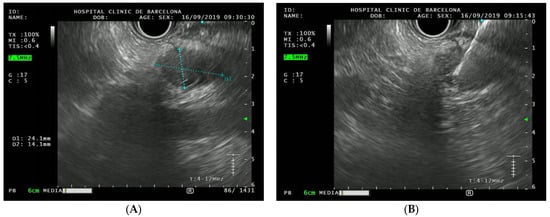

- PDAC surveillance: type of test (EUS or MRI), periodicity, findings (normal, preneoplastic lesions, cancer);